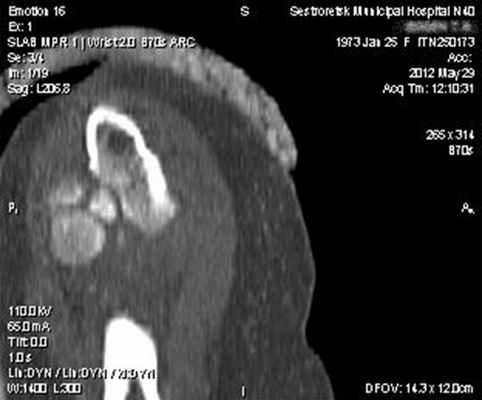

Выполнена гипсовая иммобилизация в функциональном положении. Для уточнения диагноза и предоперационного планирования пациентке выполнено КТ-исследование (рис. 2).

Данный перелом можно классифицировать по классификации Mason как тип 3, по классификации АО - 21C3. Учитывая молодой, трудоспособный возраст пациентки, высокие функциональные требования, и сложность перелома - методом лечения выбрано эндопротезирование головки лучевой кости.